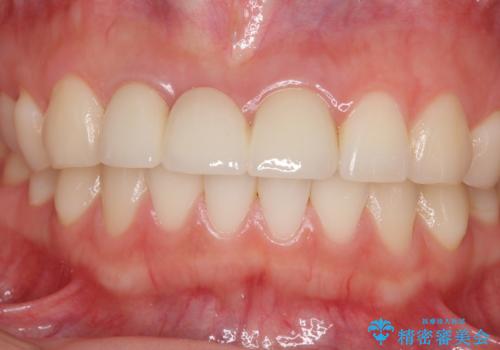

金属色の透けた感じも歯肉からの出血もなくなり、自然な仕上がりの前歯となったので、患者様には大変満足していただきました。